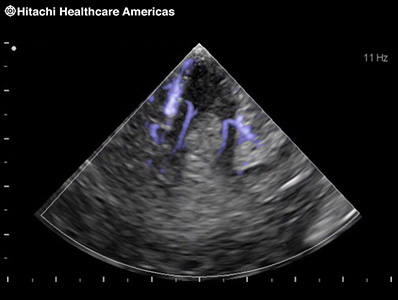

To improve understanding of blood flow information, Fujifilm Healthcare offers harmonics enhanced imaging specifically designed for use with contrast agents. The low MI contrast imaging obtained improves signal-to-noise ratio.

* In the USA, contrast-enhanced ultrasound has not been market cleared by the FDA for all imaging applications.